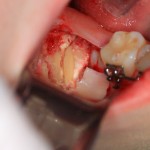

Чтобы аккуратно удалить восьмерку и не повредить соседний зуб, мы делим ее на две части. НИКАКИХ МОЛОТКОВ И ДОЛОТОВ))) Все делается, исключительно, с помощью фрез:

После чего аккуратно удаляем коронку:

А через минуту — и корни зуба. Поверьте, это очень просто, для этого не нужно прилагать каких-то усилий. Достаточно просто включить голову.

Все. зуб удален. Осталось наложить швы. Лунка зуба зашивается наглухо: